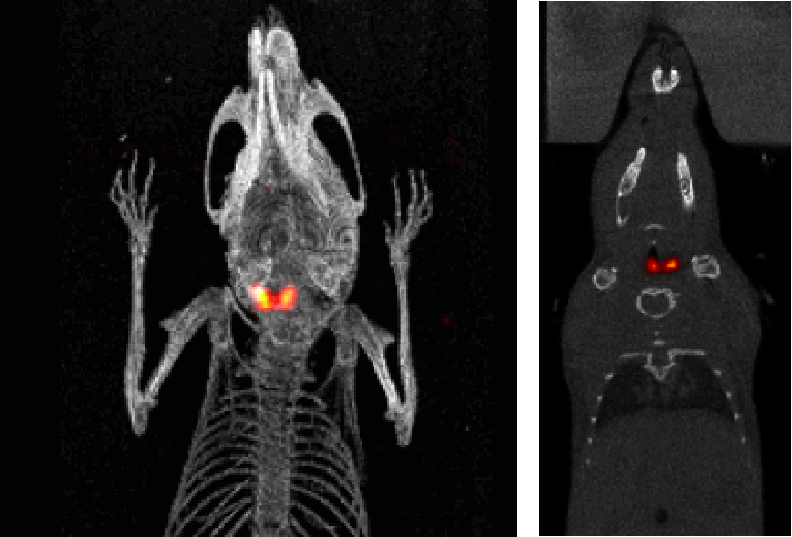

5、Thyroid SPECT imaging

I123 Mouse thyroid SPECT imaging: The mouse thyroid was detected with 9.4MBq (250μCi) I123, and the acquisition time was 30min.